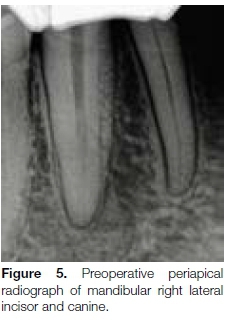

The patient, a 47-year-old female, presented with non-vital mandibular right lateral incisor and canine teeth (Figure 5, below). A preoperative limited field-of-view CBCT scan revealed that the canine had two roots and two canals bifurcating in the apical third of the tooth. The lingual canal bifurcated at an approximate 60-degree angle from the main central root canal system.